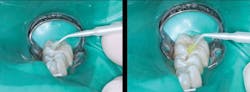

Figure 3: Tooth preparation initially cut (left) and cut deeper (right) showing inadequacy of current generation of digital bitewings to show full extent of caries as related to radiograph

Figure 5: Glutaraldehyde placed for two one-minute applications and suctioned off (left) followed by your choice of bonding agent (right)